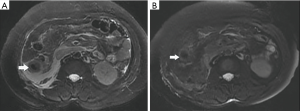

Among the AP patients, wall thickening involved duodenum (Figure 1) (27%), ascending colon (26%), stomach (20%), transverse colon (15%), jejunum (Figure 2) (14%) and ileum (6%). Dilatation of the gastrointestinal tract was seen in 8% (Figure 2, Table 2).

During treatment, 62 patients had follow up MRI examination, 16 of whom (26%) had a gastrointestinal tract abnormality on follow up examination, significantly lower than that on the initial MRI (P<0.05) (Figures 3-7). The frequencies of gastrointestinal tract abnormalities for initial and follow-up MRI examination are shown in Table 3. The difference for the frequencies of stomach, duodenum, jejunum, ileum, ascending and descending abnormal changes between before and after the treatment had statistical significance (P<0.05). There was no difference of transverse colon and bowel dilatation before and after the treatment (P≥0.05).

In the follow-up MRI exam, the structure of gastrointestinal tract restored to revert in MRI, coinciding with relief of abdominal pain, recovered appetite, cessation of hematuria, amylase recovery and anal passing gas.

In this study gastrointestinal tract wall thickening was the most common finding in AP patients. Inflammatory substances can stimulate the gastrointestinal tract in patients with AP, leading to the excessive output of gastric juices and subsequent mucosal and submucosal edema (27). Some patients exhibit a three-layer structure referred to as the “target sign” (28). Tolan et al. (29) considered this pattern acute wall edema, and noted a direct correlation with inflammatory activity. In this study we found most AP patients exhibited gastrointestinal tract wall thickening, some with a stratified appearance on MRI that was similar to the “target sign” (28). After treatment, the mural stratification resolved on follow-up MRI. Our results suggested that the thickened intestinal wall in AP patients is derived from acute wall edema and can resolve soon after treatment.